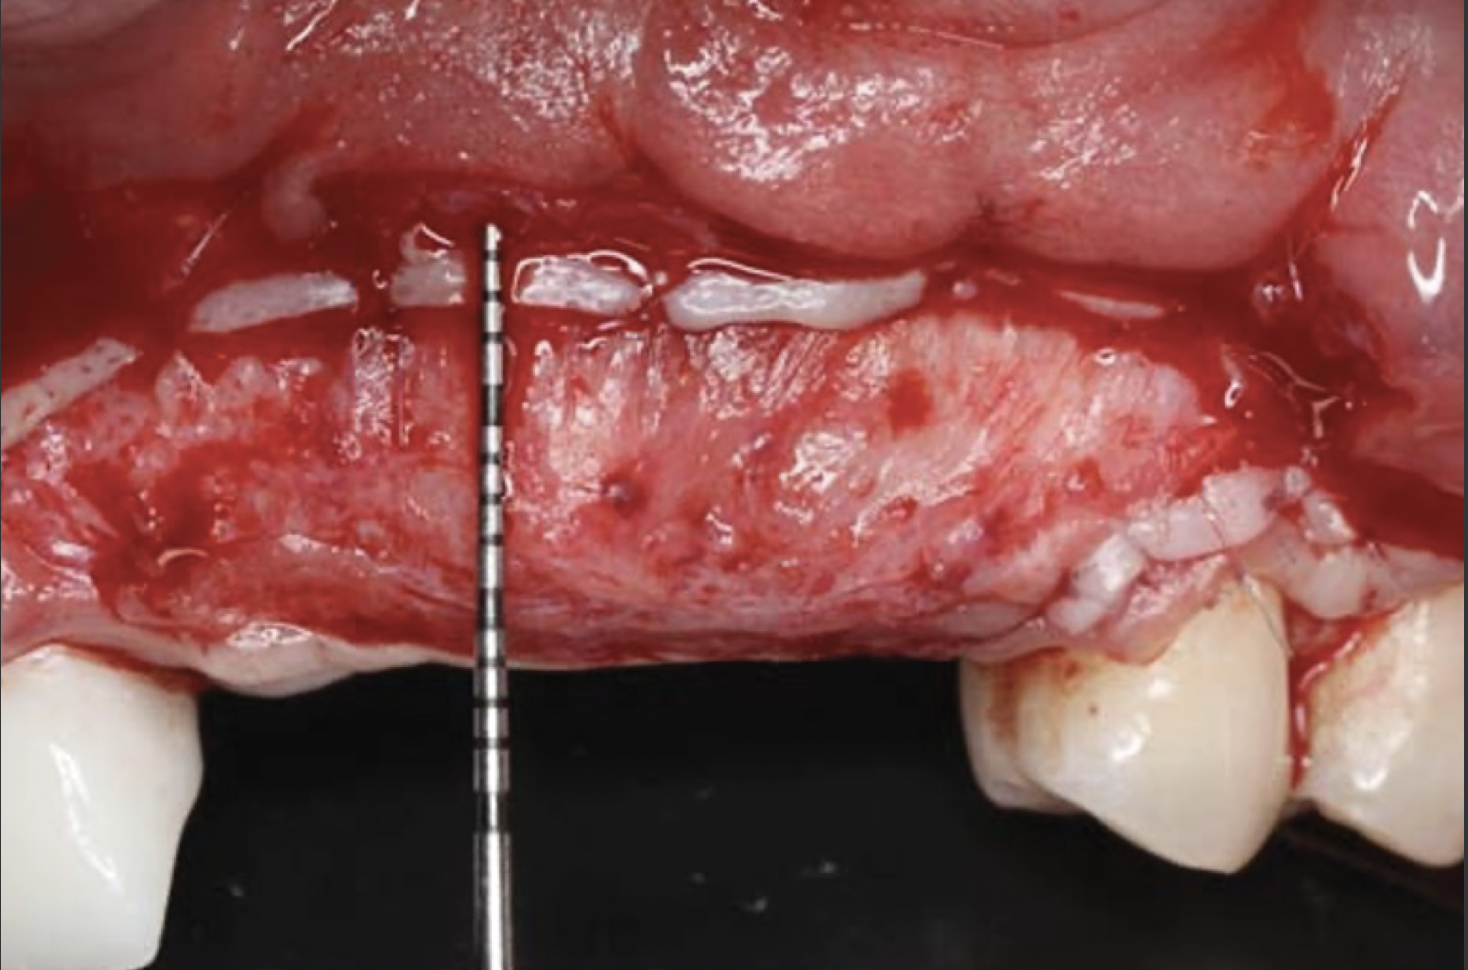

This approach was effective in increasing the horizontal and vertical soft-tissue thickness around the three implants. Nevertheless, a distortion of the MGJ was still present (Figure 13). Therefore, 3 months after the iCTG augmentation, it was decided to perform a second soft-tissue augmentation procedure with the goal of repositioning the MGJ in an adequate level on the buccal aspect, increasing the width of the keratinized mucosa at the implant sites. A modified apically positioned flap was performed (Figure 14). Two labial strip gingival grafts were harvested from the anterior mandible and maxilla and sutured onto the recipient bed with a 7-0 polyglycolic acid resorbable suture.5,17,18 The residual periostium was covered with a non-crosslinked xenogeneic collagen matrix (Figure 15).

Fig 15. Two strip gingival grafts were obtained and sutured onto the recipient bed. A xenogeneic collagen membrane was then adapted to and positioned on the denuded periosteum.

Figure 15